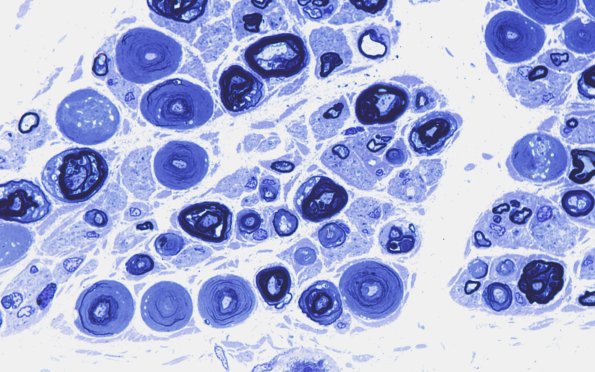

18E2 Vesicular Myelin Plastic 1

Higher magnification of image #18E1.(Toluidine blue stained one micron thick plastic embedded sections)